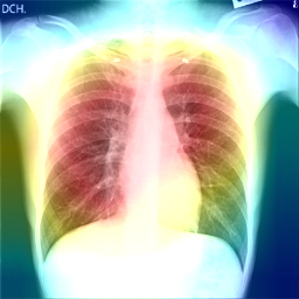

In order to compare the interpretability capacity of our model and the state-of-the-art models, we employ Grad-Cam [18] for heatmap visualizations on selected X-ray images. We show on a side-by-side basis how our model performs with superiority in Figures 4-7. We also observe that the addition of the attention block has a crucial role in focusing on the most relevant features in the images, which significantly assists the model during classification.